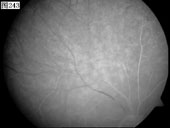

[组图]优秀眼底图片奖网上评选活动启动         ★★★

优秀眼底图片奖网上评选活动启动

优秀眼底图片奖应征作品展示